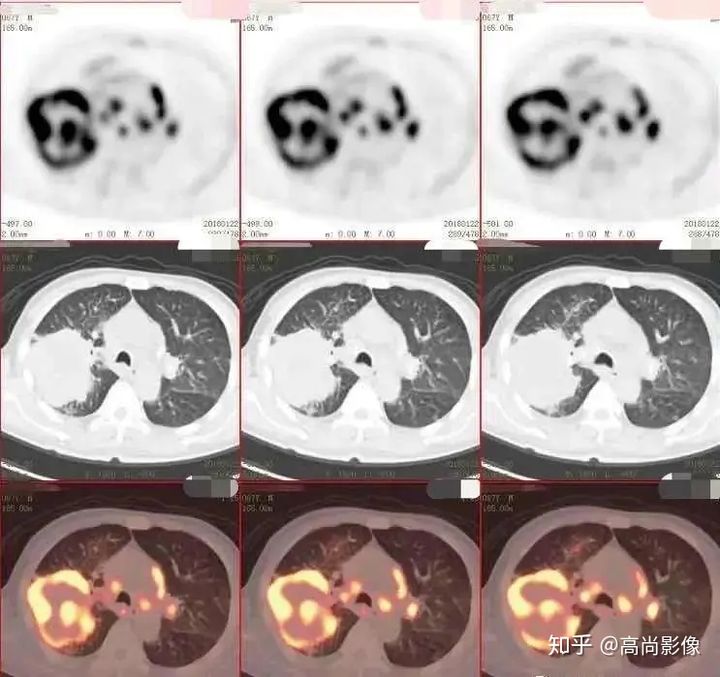

(右肺癌全身多發(fā)轉(zhuǎn)移)

(右肺上葉中央型肺癌)

方大爺?shù)腜ET/CT結(jié)果強烈提示肺癌伴全身多發(fā)轉(zhuǎn)移,已經(jīng)失去手術(shù)機(jī)會,但仍有繼續(xù)化療的機(jī)會。

基本原理:以常見的腫瘤顯像為例,惡性腫瘤細(xì)胞對FDG(葡萄糖)攝取能力大超過了正常細(xì)胞,F(xiàn)DG標(biāo)記放射性核素后注入人體,會出現(xiàn)放射性核素在腫瘤等病變組織中的濃聚,從而在設(shè)備工作站的圖像上會顯示出一個放射性濃集的區(qū)域,結(jié)合SUV等定量信息,再結(jié)合CT傳統(tǒng)的解剖影像提高病灶定位的準(zhǔn)確性,幫助醫(yī)生進(jìn)行診斷和療效評估等。

因此PET/CT顯像歸屬于“功能+結(jié)構(gòu)顯像”,就像在病變組織上裝上了GPS追蹤器,比傳統(tǒng)的醫(yī)學(xué)影像更靈敏、準(zhǔn)確、早期的發(fā)現(xiàn)病灶,可以一次性完成對全身病灶的排查,被認(rèn)為是目前腫瘤診斷和指導(dǎo)治療較好的影像學(xué)檢查之一。